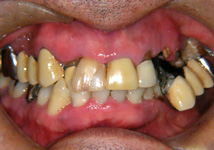

虫歯と歯周病が進行し、歯が動揺して噛みにくいということで受診されました。

歯周再生治療と審美補綴治療によってトータルコーディネートしました。

今では虫歯も治り、しっかり噛めるようになったと満足されています。 |